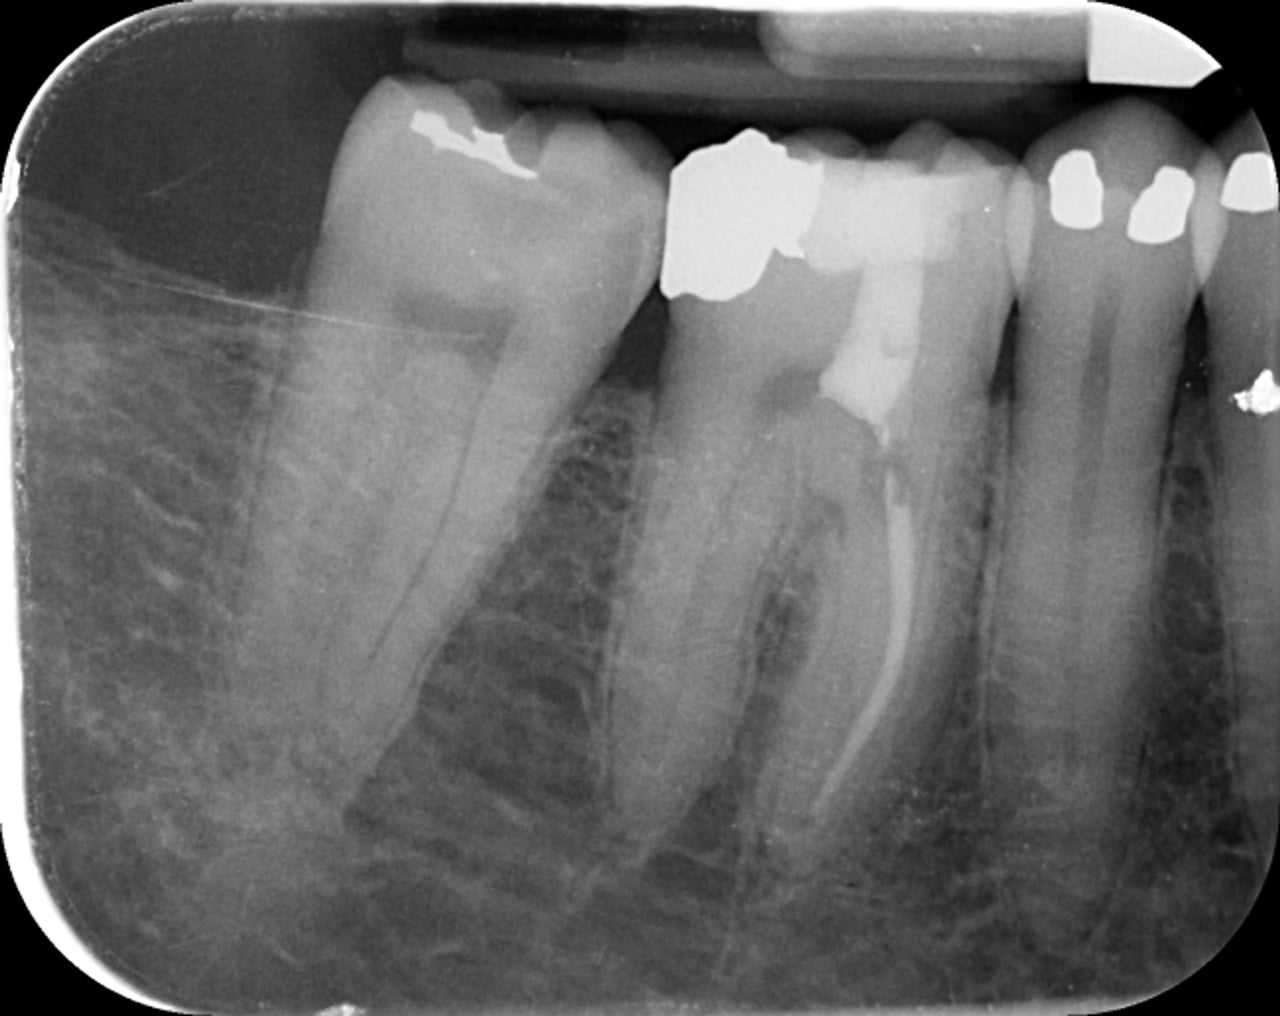

Cette lésion est clairement visible sur la radiographie préopératoire (Fig.1). Néanmoins, l’analyse de ce cliché réalisé avec un angulateur selon la technique des plans parallèles, ne permet pas de délimiter clairement les bords de cette lésion, ni d’en définir la profondeur et ses rapports avec l’endodonte de la dent concernée.

Fig.1 : Radiographie préopératoire – cliché pris selon la technique des plans parallèles avec un angulateur.

La radiographie postopératoire montre un traitement qui peut surprendre (Fig.18). Un seul canal traité, une pulpotomie partielle au niveau de la chambre et une obturation à mi-hauteur de la racine.